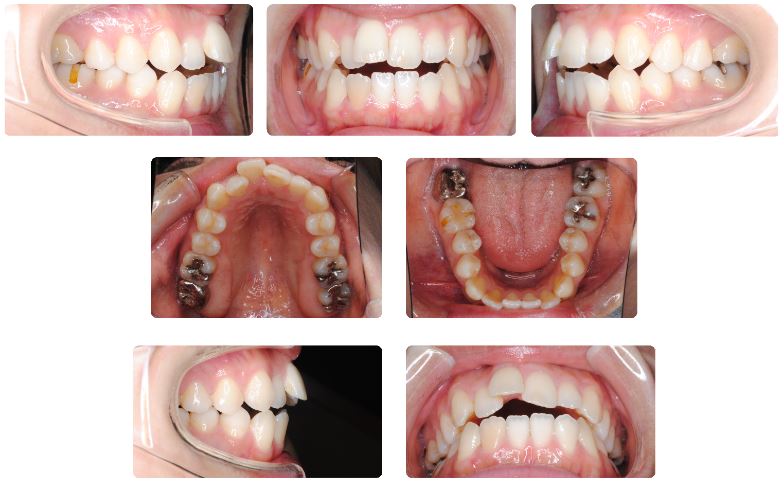

主訴:前歯でものが噛めなく見た目が気になる

初診時年齢:34歳

性別:女性

診断名:歯槽性開咬

抜歯/非抜歯:非抜歯

装置名:マルチブラケット装置

15年ほど前に他院で矯正治療を一度受けていますが、当院にて再治療希望で来院されました。

舌癖により前歯の開咬状態が再発しており、矯正治療以上に治療後に咬みあわせが安定するようにMFT(舌などのトレーニング)が必須の症例です。

上下の歯列をよく見てみますと共に歯列の幅が狭くなっています。

これは舌体が下顎歯列の中に常時納まったままの低位舌という状態の影響です。